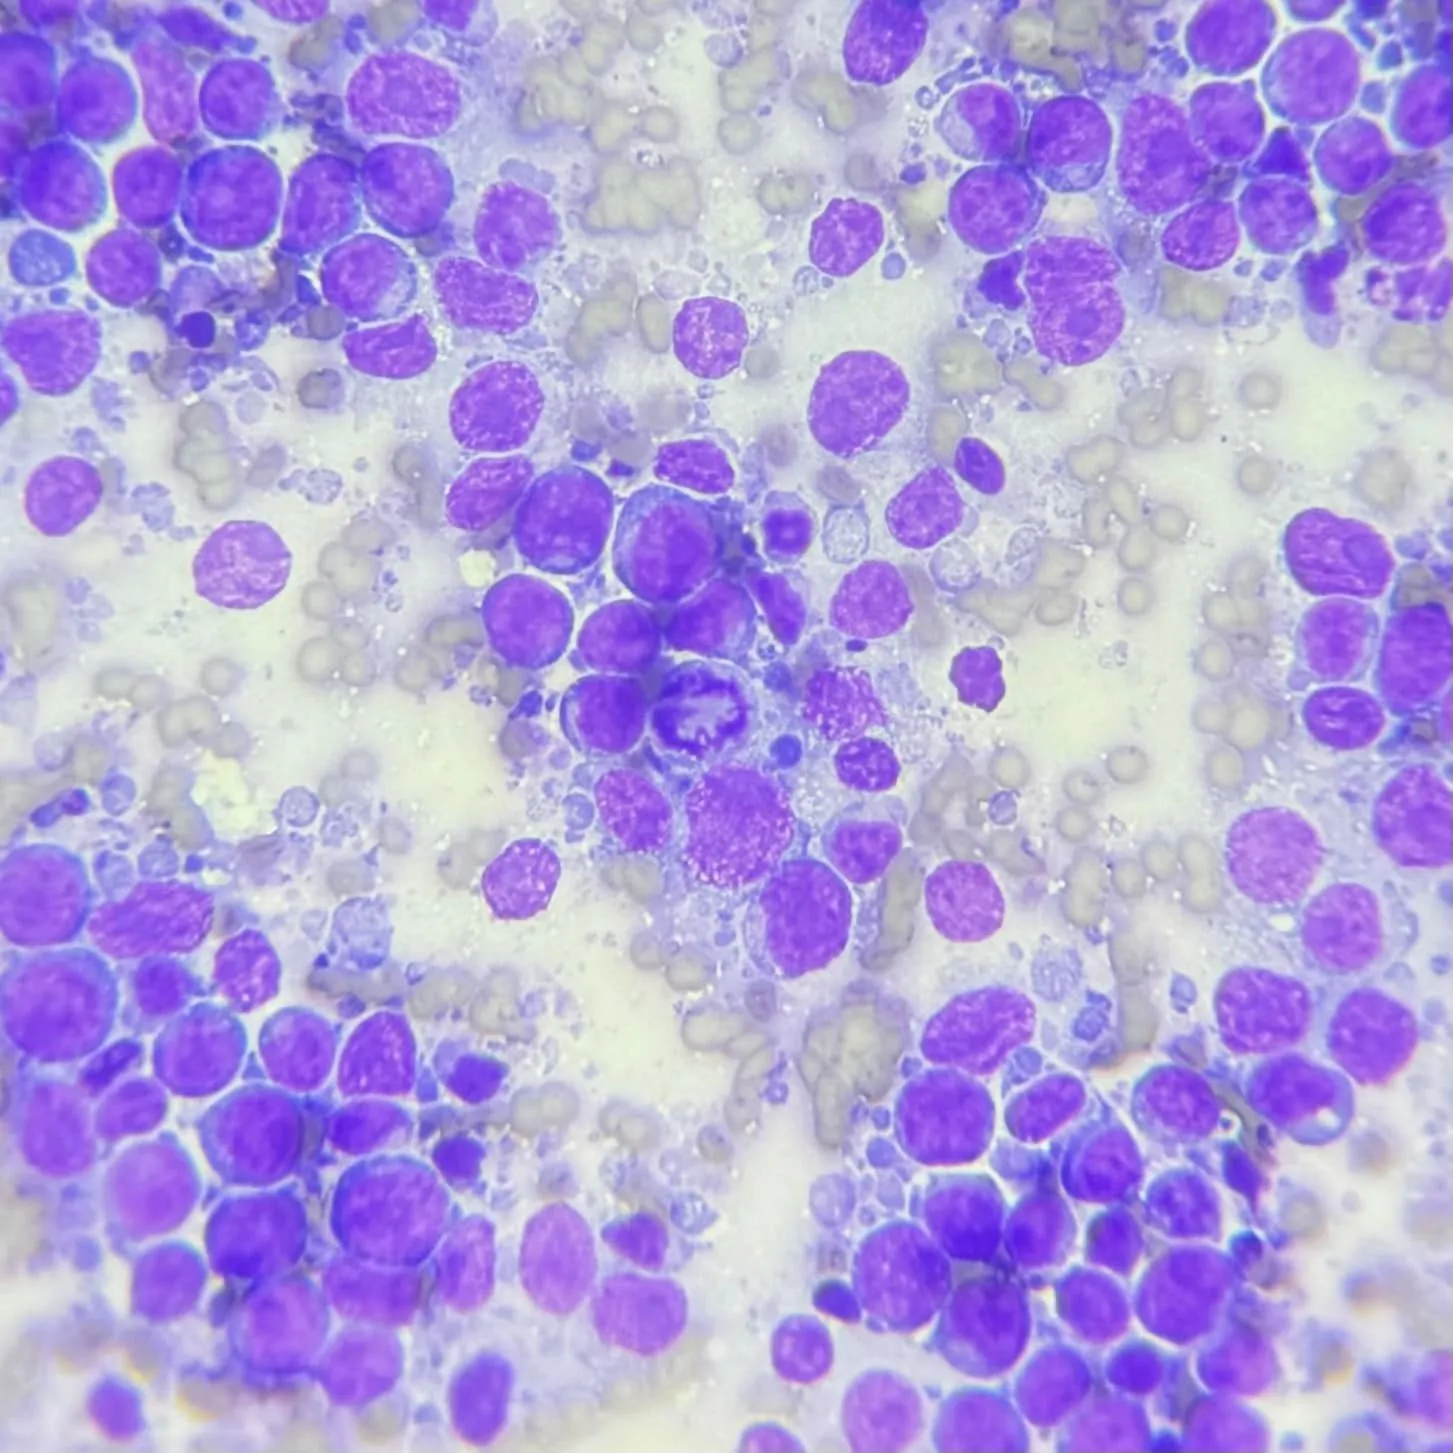

針對腫大的淋巴結、團塊,或體內病灶進行超音波導引針對腹腔腫塊或消化道壁採樣都可以確診。當然在細胞抹片的判讀上,會需要一定的經驗,且對抹片品質與採樣技巧上有一定的要求。

針對腫大的淋巴結、團塊,或體內病灶進行超音波導引針對腹腔腫塊或消化道壁採樣都可以確診。當然在細胞抹片的判讀上,會需要一定的經驗,且對抹片品質與採樣技巧上有一定的要求。